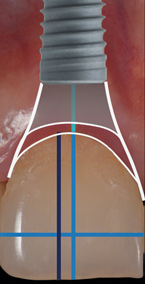

Given the importance of these hard- and soft-tissue relationships, in order to achieve an optimal esthetic and functional outcome in the anterior maxilla, it is proposed that, mesiodistally, implants should be centered in line with the gingival zenith rather than centered within the available restorative space (Figure 1 through Figure 3).

The digital wax up allowed the implant position to be planned based on the ideal prosthetic position of the final restoration (Figure 14). The planned implant position adhered to the aforementioned guidelines for ideal implant placement regarding the buccal, interproximal, and apical bone, and its platform would be located 4-mm apical to the planned restorative margin. In the coronal plane, the implant was centered with the gingival zenith in a position that was located approximately 1-mm distal to the midline of the edentulous space. Following implant planning, a tooth-supported surgical guide was designed and then 3D-printed to facilitate fully guided surgical implant placement.

(3.) Implant placement at site No. 8 that is mesiodistally centered with the gingival zenith, exhibiting a gingival contour that is harmonious with the abutment contour.

Figure 3

(21.) Postoperative periapical radiograph taken immediately after placement of the implant at site No. 8 demonstrating implant positioning centered with the planned location of the gingival zenith and two titanium alloy tacks that were used to stabilize the resorbable membrane apically.

Figure 21